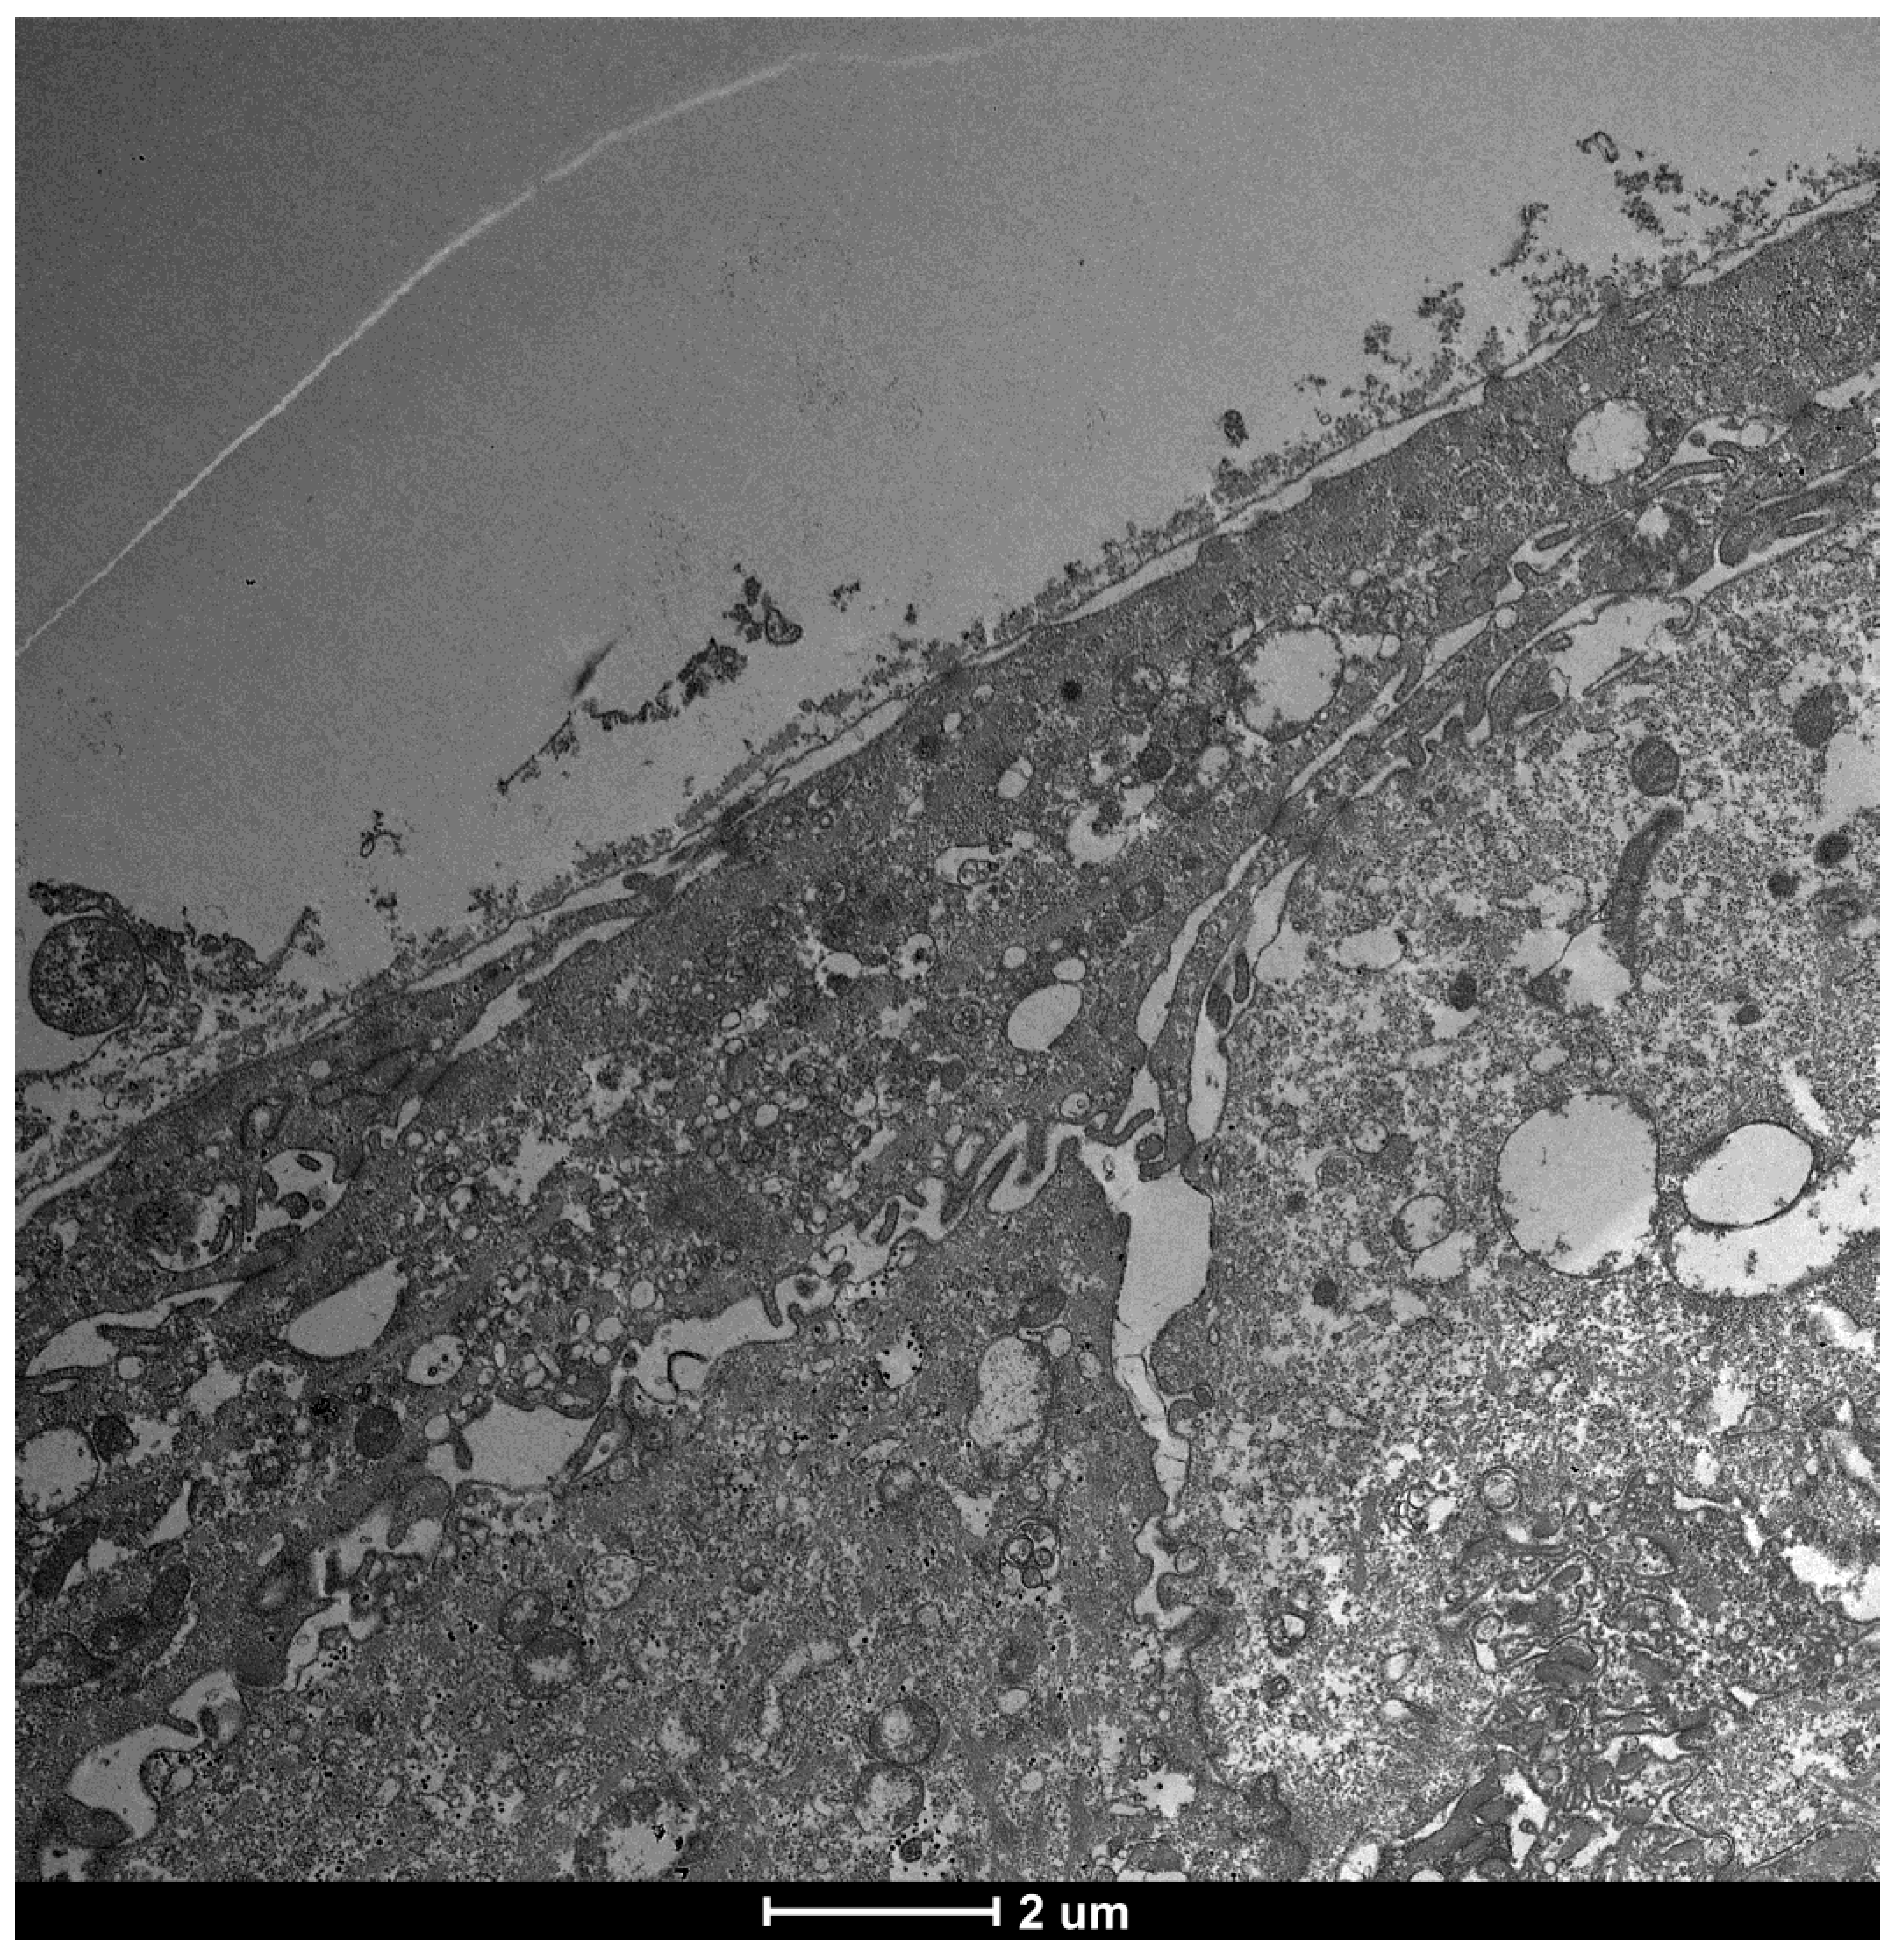

| TEM Evaluation Table | ||||

| Grade 0 | Grade 1 | Grade 2 | Grade 3 | Grade 4 |

| Presence of glicocalyx and presence vescicular transport | Reduction of Glicocalyx and presence of vescicular transport | Absence of glicocalyx and reduction of vescicular transport | No glicocalyx, No vescicular transport, Reduction of lenght of microvilli | flattening of the plasma membrane, absence of exchange with the outside |